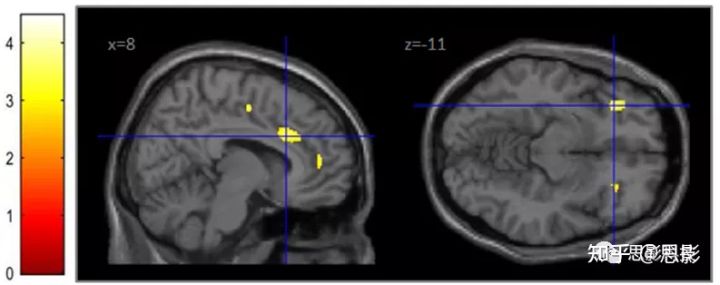

- 3.2 灰质体积GMV

与对照组相比,SPA患者在左侧前岛叶(x = 27, y = 17, z =−5, Z = 3.68, k = 326),左侧下颞叶(x = −27, y = −9, z = −48, Z = 3.99, k = 176),左侧海马旁皮质(PHC, x = −14, y=−36, z =−3, Z = 3.90, k = 197)的GMV减小;在左侧边缘上回皮层(x = −44, y = −75, z = 9, Z = 3.91, k = 138)的GMV增大。如图1所示。

图1 GMV的两组比较

左图:与对照组相比,SPA患者的GMV存在差异。左侧前岛叶和左侧PHC的GMV较低。SPA患者左缘上回GMV增加。*表明这些区域在BDI评分共变异中没有存活。所示为二级ANCOVA结果,p < 0.001未经校正的身高,k > 80体素。

右图:与对照组相比,SPA患者的内在活动存在差异。SPA患者右侧ACC活性较低。所示为二级ANCOVA结果,p < 0.001,未校正,k > 5个体素。颜色条表示t值。

- 3.3 ALFF

与对照组相比,SPA患者右侧ACC的ALFF较低(x = 9, y = 27, z = 27, z = 4.72, k = 14体素);参见图1。与对照组相比,在SPA中没有发现ALFF增加的区域。